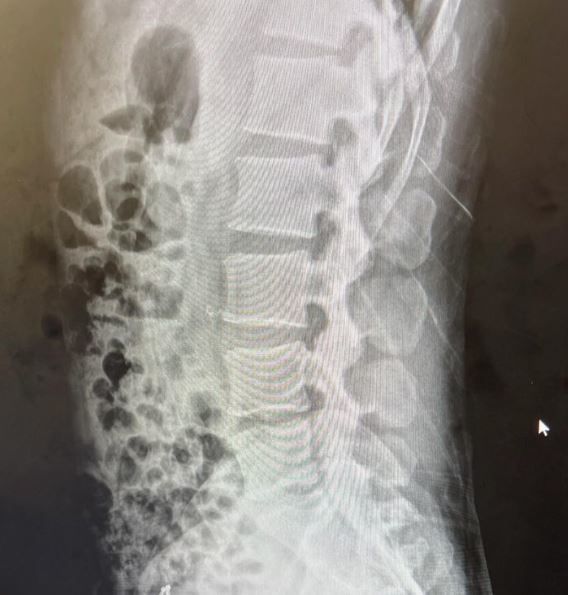

최근 홍석천은 인스타그램에 허리 엑스레이 사진을 공개했다. 그는 허리디스크로 고통을 느끼고 있다.

홍석천은 "디스크가 안 좋단다"라며 "오랫동안 참 애썼다. 고통은 둘째고 왠지 서글프다"라고 말했다.

허리 디스크 인증 사진 / 홍석천 인스타그램